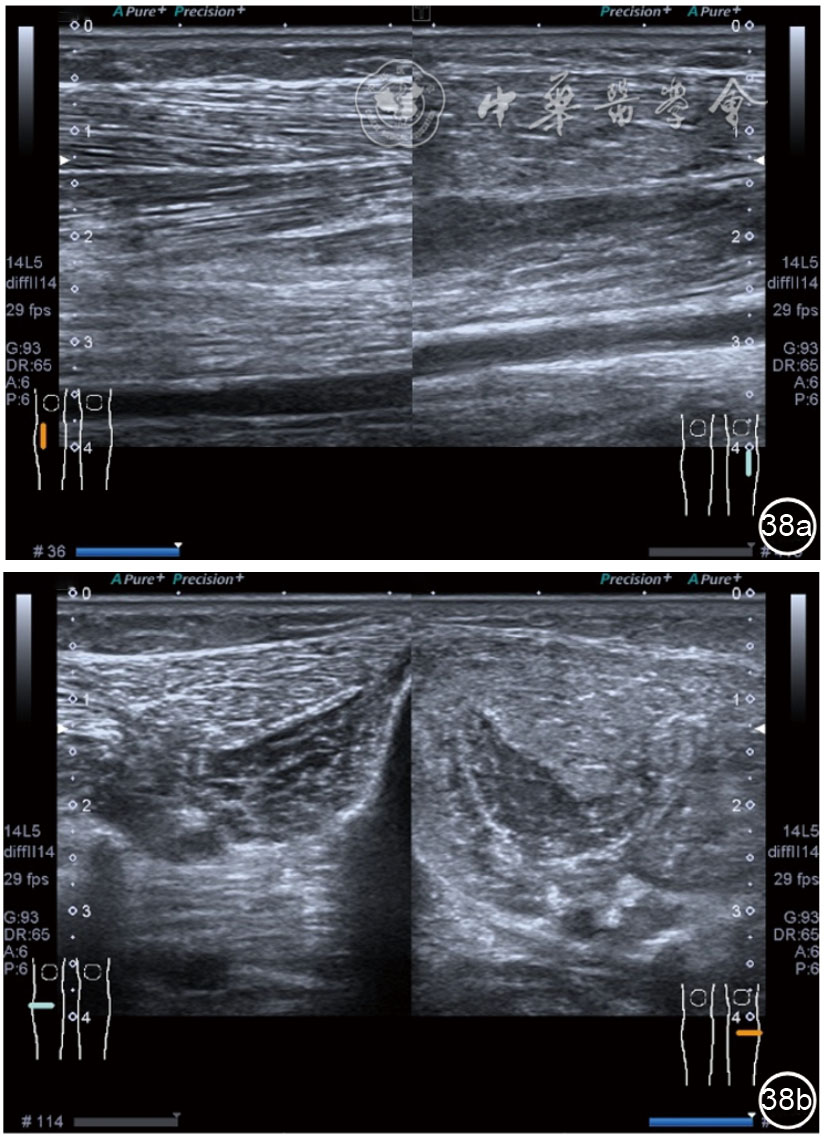

4.腓总神经分支卡压的治疗。常见腓浅神经、腓深神经感觉支卡压。主要表现为足背侧的感觉减退。腓深神经只支配第一、二足趾之间的感觉,腓浅神经支配的感觉区域较多,第一、二足趾之间外的足背感觉均由腓浅神经支配,根据感觉障碍区域确定卡压神经,超声可以明确卡压部位和原因。超声可显示卡压神经增粗,回声减低,局部软组织回声不均匀等(图4445)。治疗以液压松解药物注射为主。以腓深神经为例进行介绍。常见卡压部位在小腿和足背部。根据卡压部位不同,患者采取不同的体位。如果在小腿部采用平卧位,膝关节伸直位即可。穿刺区域常规消毒,探头涂抹耦合剂后套入无菌手套碘伏消毒或使用无菌耦合剂。将探头置于患者皮肤表面,小腿部位采用短轴扫查,确定神经卡压最明显的部位后,用一次性5 ml注射器,应用25G注射针头抽吸0.5%利多卡因4 ml+地塞米松3 mg平面内进针到达神经周围,注意回抽无血液回流后进行注射(图46),完成注射松解,拔出针头,局部压迫3分钟,创可贴覆盖。如果在足背部可以采取平卧位,屈髋、屈膝将足平放于治疗床面。治疗前准备同小腿部,采用长轴显示神经,确定神经卡压最明显的部位后,用一次性5 ml注射器,应用25G注射针头抽吸0.5%利多卡因2 ml+地塞米松1 mg平面内进针到达神经表面进行注射(图47),完成注射松解,拔出针头,局部压迫3分钟,创可贴覆盖。

图44 腓浅神经在小腿中下1/3筋膜穿出部位卡压的短轴和长轴超声图像

图45 腓浅神经在小腿中下1/3筋膜穿出部位局部软组织回声不均匀超声图像